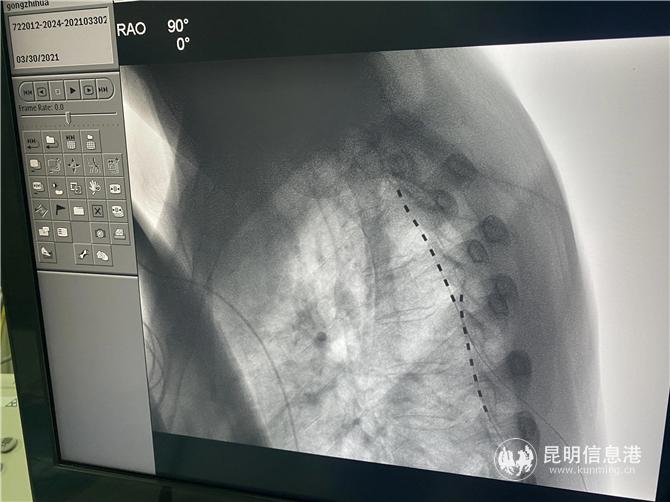

2021年2月,龚志华入院,龚会军详细询问了病史,反复评估,听取科内的讨论和外省专家的意见,结合病症,诊断为复杂性局部痛综合征(CRPS),但因疼痛范围较广、疼痛区域变化、疼痛时间较长,加之,患者由于多次手术,脊柱椎管等解剖结构严重改变并粘连,在手术方案的选择上带来了难度。经科内反复讨论病例,决定用脊髓鞘内注吗啡和安置脊髓电刺激两种新技术来比较疗效,最终一致决定采用创伤心主任朱晓松教授意见,采用脊髓电极置入术进行治疗。

3月31日,在多学科团队的配合下,龚会军在介入杂交手术室、用局麻下为患者植入电极,由于患者之前的陈旧性损伤,患者的脊柱结构黏黏严重,给上行穿刺造成了极大的困难,同时,术中患者的疼痛位置又发生了变化,龚会军团队及时调整,术中测试患者疼痛区域全覆盖。术后,龚志华的疼痛明显缓解。(昆明信息港 记者孙红亮)